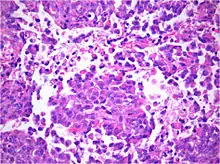

AT/RT and rhabdoid tumor share the term "rhabdoid" because under a microscope, both tumors resemble rhabdomyosarcoma.

Histology

The tumor histopathology is jumbled small and large cells. The tissue of this tumor contains many different types of cells including the rhabdoid cells, large spindled cells, epithelial and mesenchymal cells, and areas resembling primitive neuroectodermal tumor (PNET). As much as 70% of the tumor may be made up of PNET-like cells. Ultrastructure characteristic whorls of intermediate filaments are seen in the rhabdoid tumors (as with rhabdoid tumors in any area of the body). Ho and associates found sickle-shaped embracing cells, previously unreported, in all of 11 cases of AT/RT.[16]